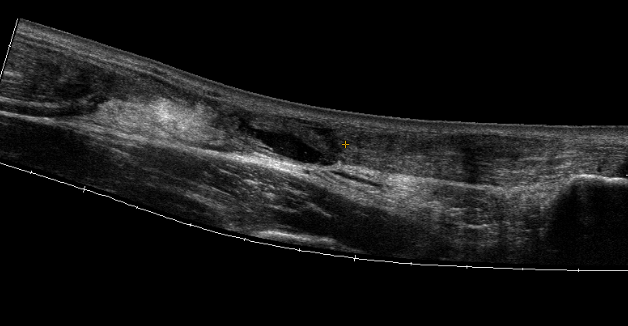

Ultrasound

Diagnose rupture and check reduction of tendon ends with plantarflexion

Aminlari et al J Emerg Med 2021

- systematic review

- ultrasound 95% sensitive and 99% specific for complete rupture